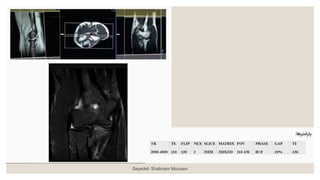

◦ ‫آگزیال‬ T2* MEDIC ‫ضخامت‬ ‫با‬ ۳ ‫میلیمتری‬ : ◦ ‫به‬‫و‬ ‫بورونال‬ ‫صدحه‬ ‫رو‬ ‫را‬ ‫آگزدال‬ ‫مقاطع‬ ‫و‬ ‫داخلکی‬ ‫برککدل‬ ‫اپکی‬ ‫از‬ ‫بکه‬ ‫خطکی‬ ‫موازات‬ ‫بچیریک‬ ‫گذرد‬ ‫می‬ ‫خارجی‬ . ‫را‬ ‫مقکاطع‬ ‫موقعیکت‬ ‫بریک‬ ‫چک‬ ‫نیز‬ ‫ددد‬ ‫صدحه‬ ‫دو‬ ‫در‬ . ‫صکدحه‬ ‫در‬ ‫اساخوا‬ ‫به‬ ‫ومود‬ ‫مقاطع‬ ‫بریک‬ ‫چک‬ ‫ساجیاال‬ ‫باشرک‬ ‫بادک‬ ‫ساوک‬ ‫و‬ ‫بازو‬ . ‫هکا‬ ‫ش‬ ‫بک‬ ‫تعکاد‬ ‫تکا‬ ‫فوسا‬ ‫انو‬ ‫اوسن‬ ‫از‬ ‫باالت‬ ‫ش‬ ‫ب‬ ‫دو‬ ‫بادک‬ ‫راددکال‬ ‫وزداه‬ ‫توب‬ ‫از‬ ‫ت‬ ‫پادی‬ ‫مقطع‬ ‫دو‬ ‫دهک‬ ‫پوشش‬ ‫را‬ . ‫و‬ ‫باال‬ ‫در‬ ‫اشباع‬ ‫بانک‬ ‫گذاشا‬ ‫وق‬ ‫وک‬ ‫پاسسیشک‬ ‫آرتیدنکت‬ ‫از‬ ‫مقکاطع‬ ‫پادی‬ Seyedeh Shabnam Mousavi